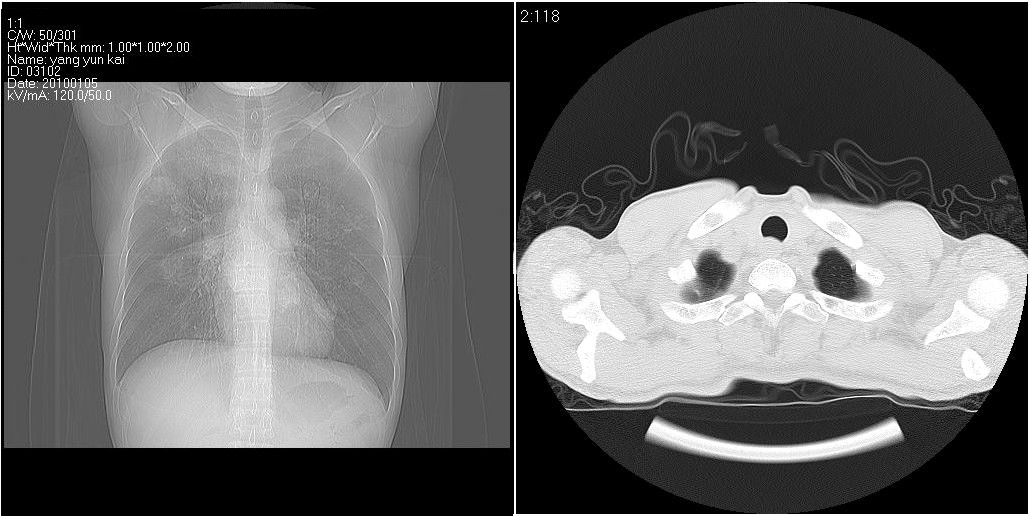

标题: CT23980:男性,47岁。近来咳痰、咳血,血沉增快(40左右),

男性,47岁。近来咳痰、咳血,血沉增快(40左右),痰中未检出结核杆菌。

双肺继发性肺结核

两肺继发性肺结核并多发性结核球形成,部分病灶内空洞形成。